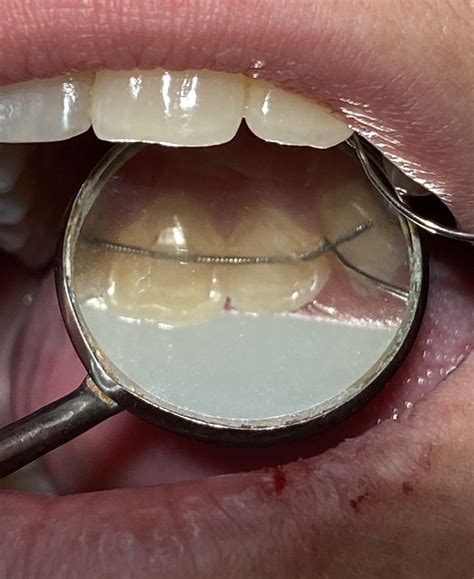

El tejido periodontal que sostiene los dientes necesita tiempo para estabilizarse después del movimiento ortodóncico. Durante ese periodo, los dientes están más susceptibles a volver a su posición inicial, lo que se conoce como recidiva. Para ello, se sitúa un alambre, más comúnmente entre canino y canino de la mandíbula y/o del maxilar, en la parte interior de los dientes (lingual y palatino). Este alambre queda unido a cada uno de los seis dientes mediante composite. El alambre se prepara previamente y se va adaptando a la forma de los dientes del paciente. Esto es conocido como: retenedor lingual, y evita que los dientes corregidos mediante ortodoncia se muevan a su posición original.